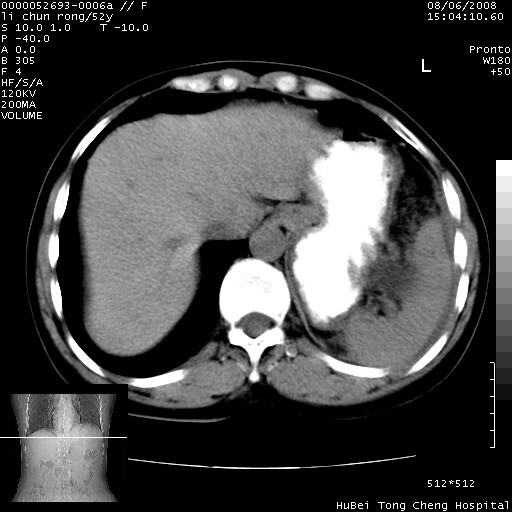

以下是引用云翔在2008-8-7 6:20:00的发言:[br]胰尾部囊性病变,考虑假囊肿,结合实验室检查疾病史

以下是引用zjzjr在2008-8-7 8:38:00的发言:[br]支持胰腺炎伴假囊肿形成,左肾小囊肿.少量腹水.

以下是引用随光逐影在2008-8-7 9:12:00的发言:[br]1)考虑胰腺炎伴假性囊肿形成可能性大;胰腺囊腺瘤待排。2)左肾小囊肿。3)少量腹水。